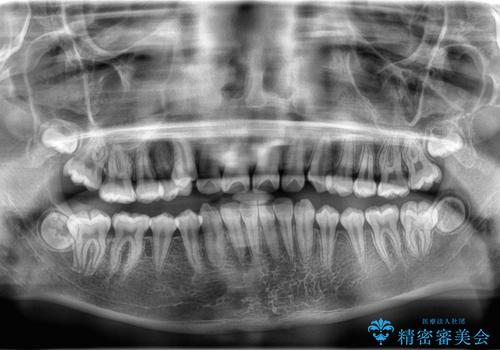

矯正の精密検査の結果上顎左右4番の計2本を抜歯し、審美性に配慮したワイヤー矯正装置(審美装置)を用いて治療を行いました。

八重歯などの歯列のデコボコが綺麗に改善され、患者様にも大変喜んでいただけました。また、咬み合わせが深い「ディープバイト」も併せて改善し、見た目だけでなく機能面でもバランスの取れた咬合を獲得しています。